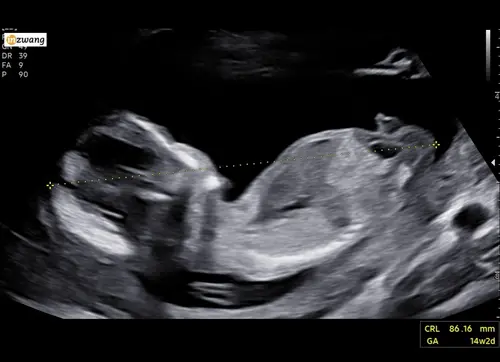

Kan iemand mij helpen bij deze? 14+2 volgende week Officele geslachtsecho maar toch erg nieuwsgierig wat jullie denken hihi:)